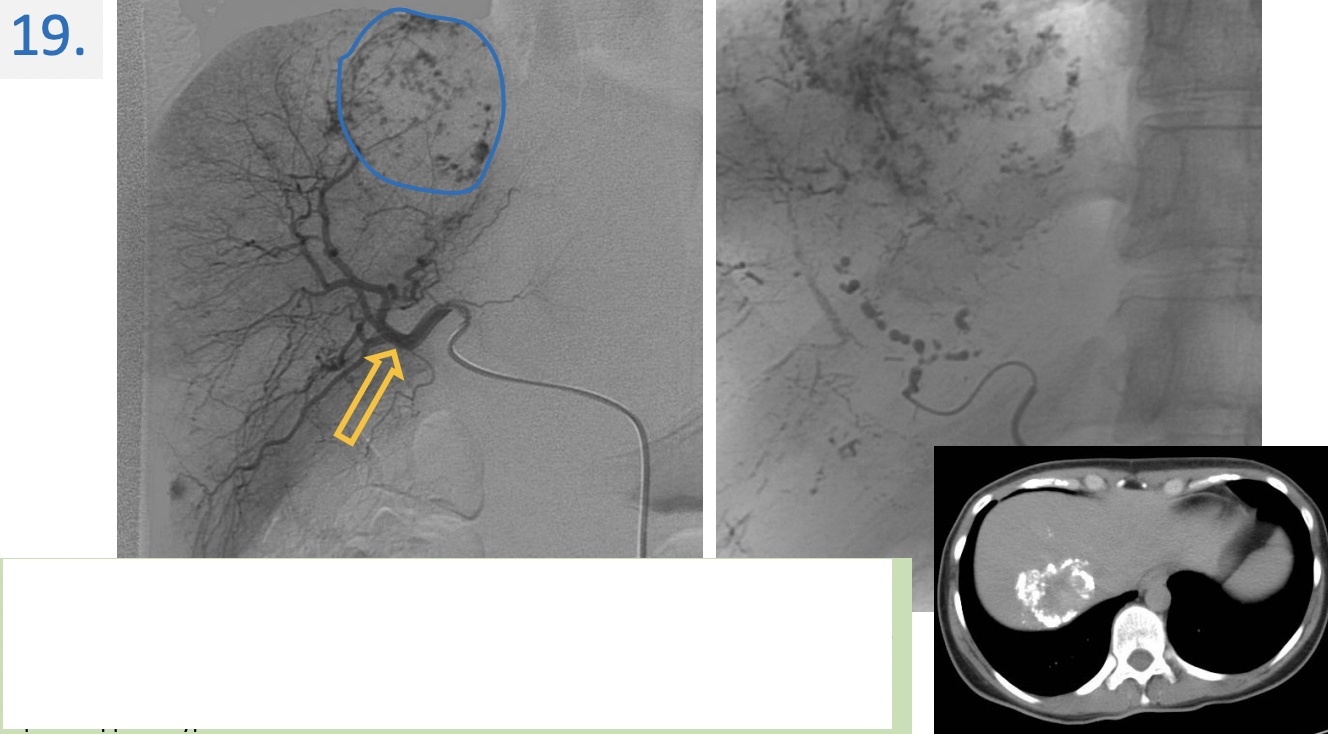

19